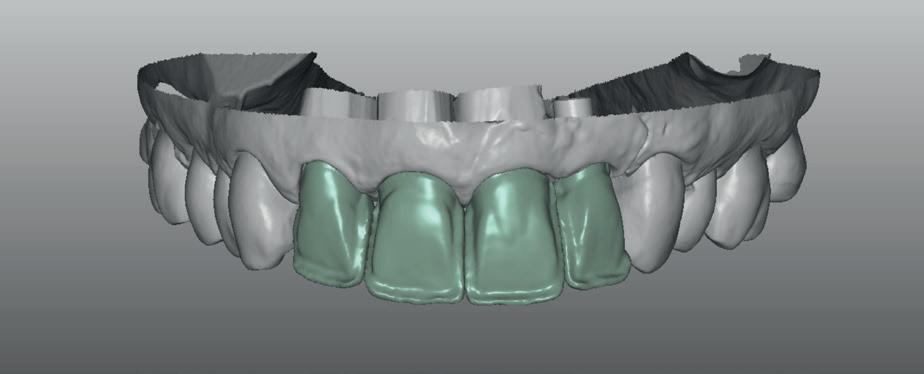

In de laatste stap wordt gekeken naar de uiteindelijke vorm van de te vervaardigen restauratie(s). Deze bepaalt de 3D-locatie van het implantaat. Deze informatie kan gebruikt worden bij het plaatsen van het implantaat en geeft ook de input voor het vervaardigen van het operatiesjabloon. Daarnaast kan de tijdelijke voorziening al gemaakt worden in de geplande vorm zodat de patiënt een goede indruk kan krijgen van het beoogde eindresultaat. Dit biedt de mogelijkheid voor de patiënt om in de tijdelijke fase

Het botdefect wordt geaugmenteerd met een allograft (Biohorizons MinerOss A). Om dit volume te stabiliseren, wordt een titanium versterkt membraan aangebracht (Cytoplast ti-reinforced d-PTFE membraan) met daaroverheen een collageen membraan (Mem-Lok collagen matrix). Na sluiting van de flap wordt de 4-delige PMMA brug, die al is gefreesd in het laboratorium naar aanleiding van de planning, gerelined en geplaatst met een tijdelijk cement (foto 9-14).

Na vier maanden wordt er een CBCT gemaakt om het botvolume te kunnen beoordelen en een digitale planning te kunnen maken voor het plaatsen van het implantaat. Tevens wordt de stabiliteit van de botpieken op het buurelementen bekeken (foto 15 en 16).

Er wordt een afdruk of een intra-orale scan genomen van de situatie met tijdelijke voorzieningen en de geprepareerde situatie. Ook mag een portretfoto en mondfoto niet ontbreken. Al deze informatie gaat naar het laboratorium zodat de onderstucturen van de restauraties gemaakt kunnen worden (foto 26).